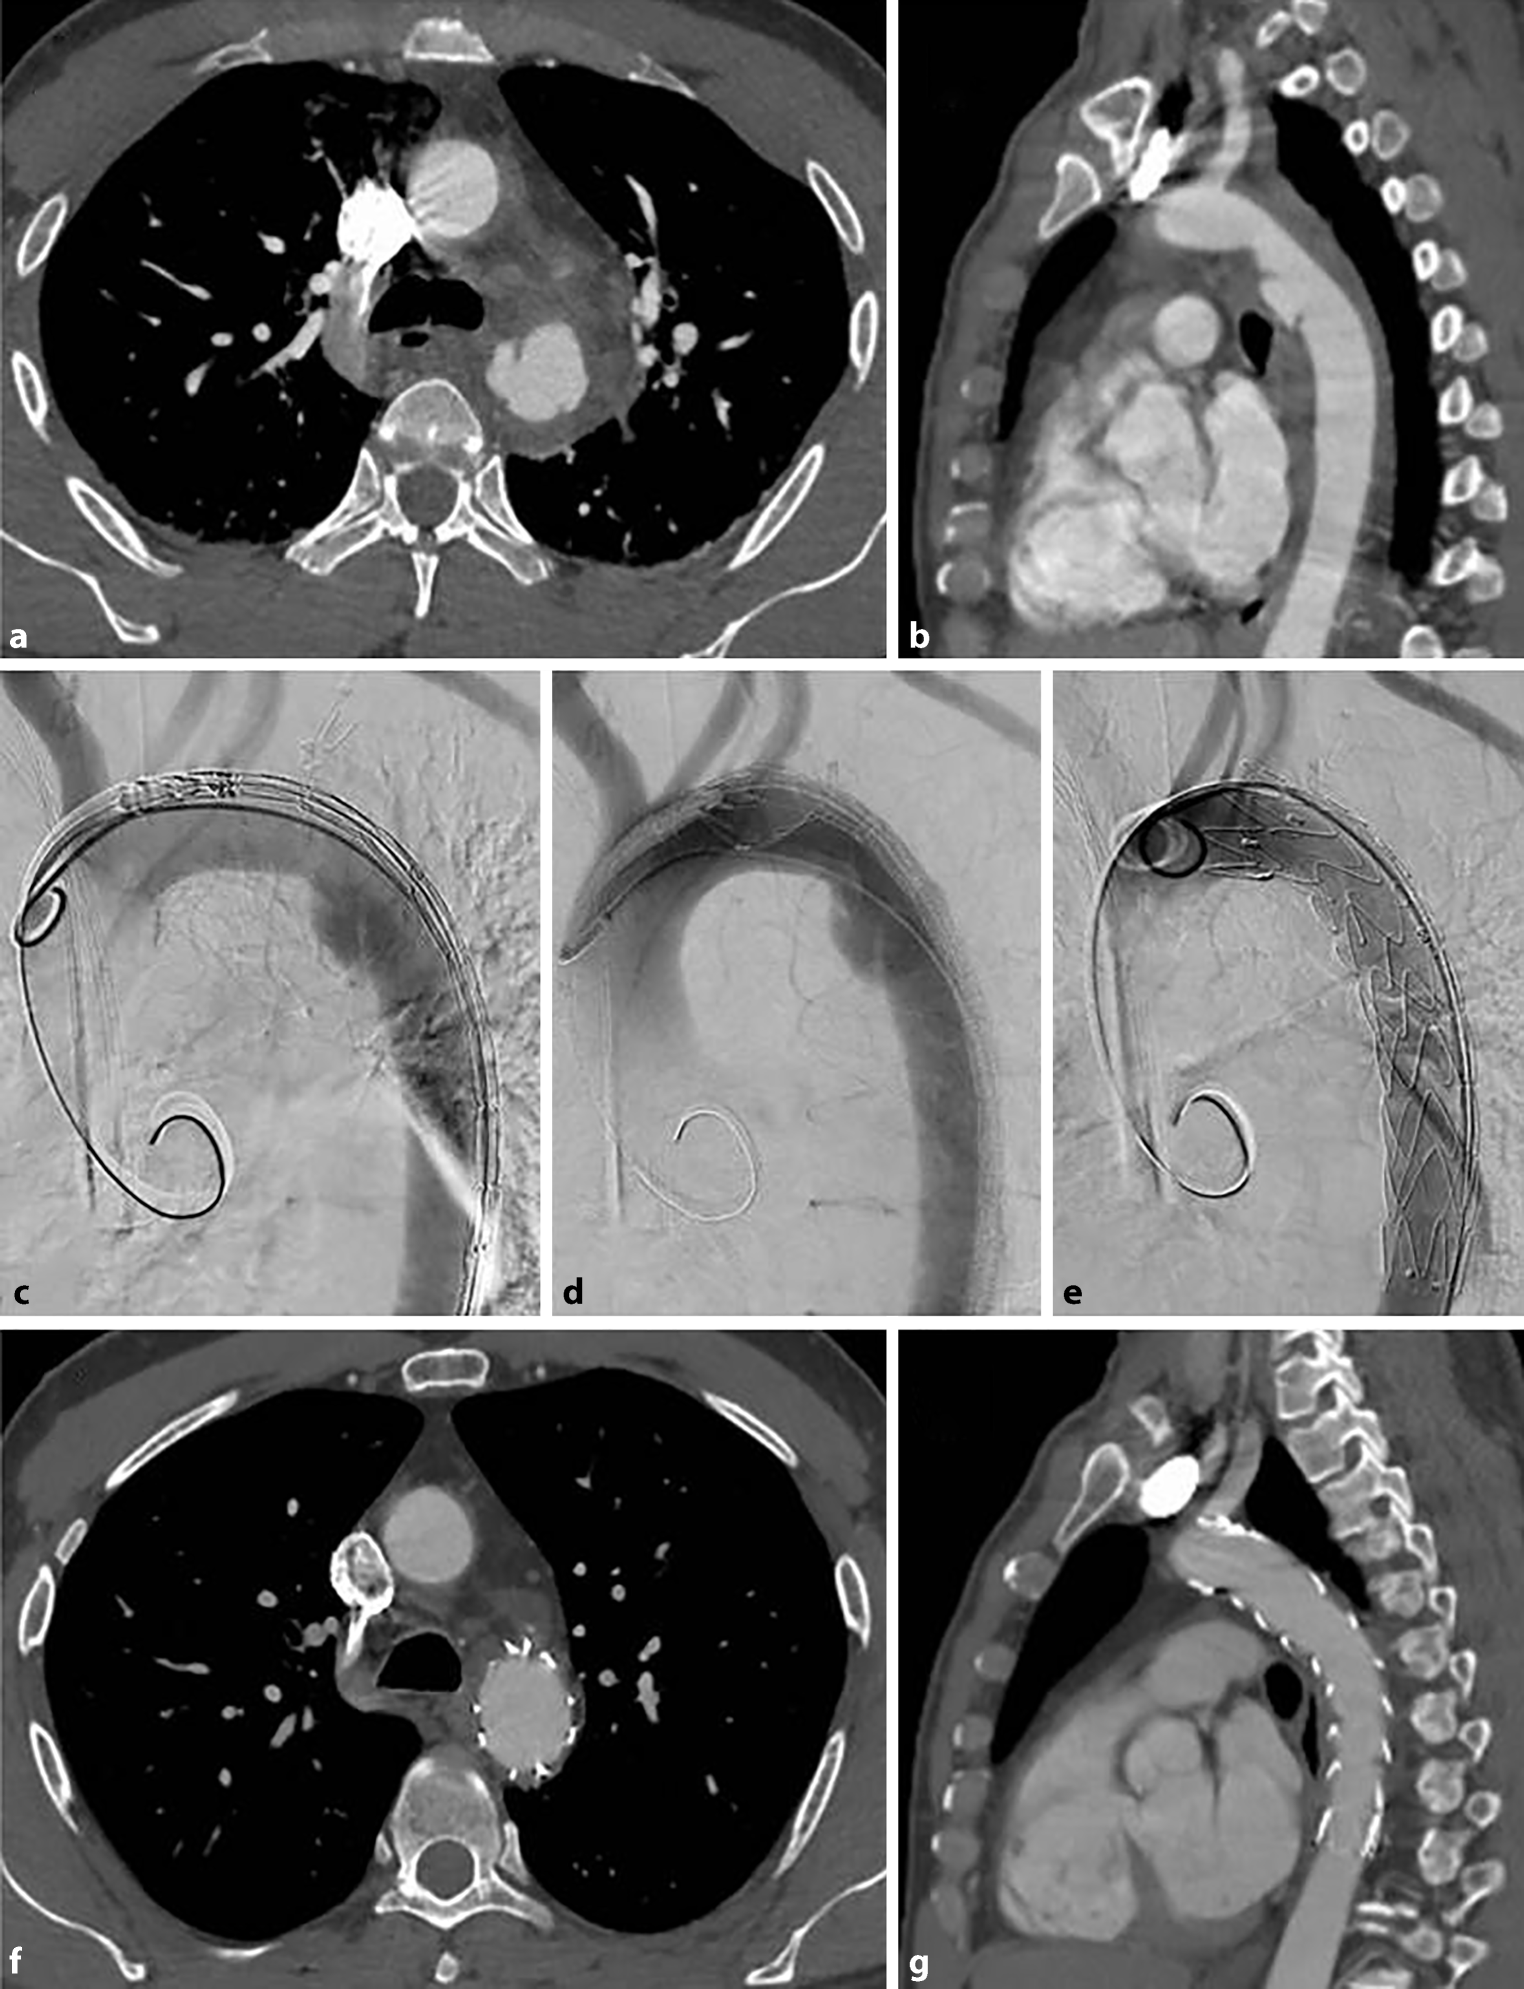

Diese Daten stammen jedoch fast ausschließlich von nicht-vergleichenden Fallserien, retrospektiven und nicht-randomisierten Studien. Der case mix (Verteilung der Schweregrade), nicht standardisierte Operationsverfahren und Patientenselektion sowie Publikationsbias erklären teilweise sehr unterschiedliche Ergebnisse und erschweren einen detaillierten Vergleich beider Verfahren [43, 64]. Abb. 2 zeigt den typischen Fall einer Grad 3 Ruptur mit endovaskulärer Versorgung.

ab 51 Jahre alter Mann mit traumatischer Aortenruptur loco typico bei Z. n. Motorradunfall mit begleitender Leberruptur und Beckenfraktur. Gedeckte Ruptur mit Pseudoaneurysma und periaortalem Hämatom. cf Typische interdisziplinäre endovaskuläre Versorgung mittels Stentgraft. fg Kontroll-CT nach 6 Monaten ohne Hinweis für Endoleaks